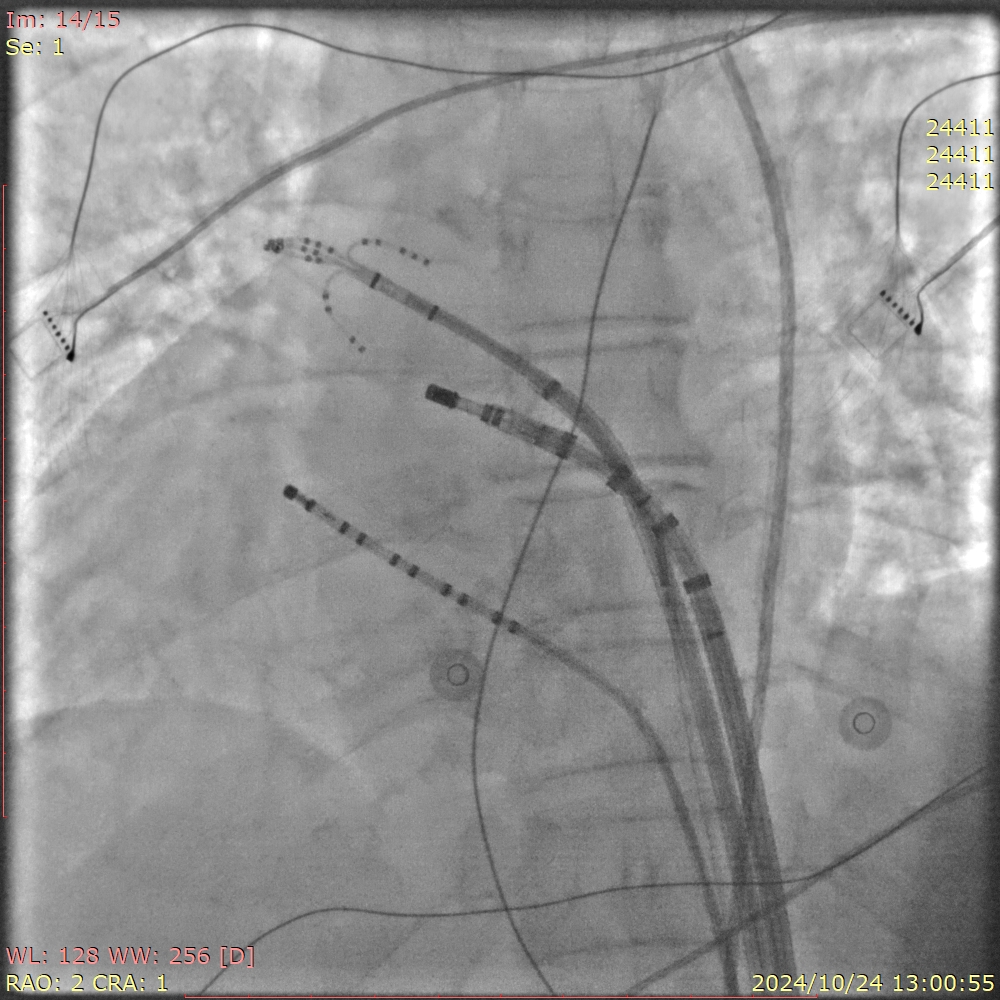

手术过程中,王洪涛教授亲自操刀,充分利用CARTO 3三维标测系统,实现了精准定位和消融,成功为患者实施了房颤射频消融术。随后,团队又克服了镜面右位心带来的操作困难,使用新一代国产左心耳封堵器LACbes成功完成了左心耳封堵术,有效预防了卒中的发生。王洪涛教授解释:“房颤射频消融术能够消除房颤的症状,而左心耳封堵术则能够闭合房颤患者血栓发生的根源部位,两者结合能够大大降低患者的卒中和出血风险。”

整个手术过程历时数小时,团队凭借精湛的技术和丰富的经验,确保了手术的顺利进行。术后,患者生命体征平稳,无并发症发生,恢复情况良好。王洪涛教授对手术效果表示满意:“患者的恢复情况非常理想,这标志着我们医院在复杂心律失常疾病治疗方面迈上了新的台阶。”